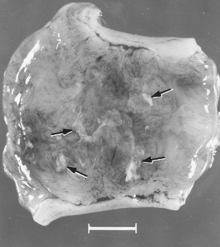

Macroscopic changes of embryos are death followed by resorption of fluids (Fig. 4) and then soft tissues (Fig. 5). Virus and viral antigen are widely distributed in tissues of infected embryos and their placentas,[81] and it is probable that microscopic lesions of necrosis and vascular damage, subsequently described for fetuses, also develop in advanced embryos.

There are numerous macroscopic changes in fetuses infected before they become immunocompetent (Fig. 6). These include a variable degree of stunting and sometimes an obvious loss of condition before other external changes are apparent; occasionally, an increased prominence of blood vessels over the surface of the fetus due to congestion and leakage of blood into contiguous tissues; congestion, edema, and hemorrhage with accumulation of serosanguineous fluids in body cavities; hemorrhagic discoloration becoming progressively darker after death; and dehydration (mummification). Many of these changes also apply to the placenta. Microscopic lesions consist primarily of extensive cellular necrosis in a wide variety of tissues and organs[92][95] (Fig. 7A). Inflammation[95] and intranuclear inclusions[92] also have been described.